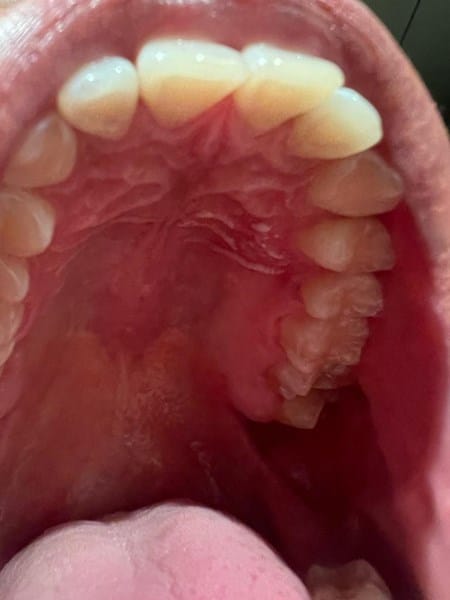

Pequeñas líneas blancas en el paladar duro, ¿Qué son?

Tengo unas pequeñas líneas blancas en el paladar duro, en un inicio pensé que fuese por alguna quemadura a algo que comí, pero al acercarme me di cuenta que estaba blanco y no parece ser un afta solo es en una pequeña area del lado izquierdo del paladar duro, todo el resto del paladar está sano, no me duele ni arde en el área, se siente igual que el resto del paladar, tampoco he tenido malestar físico o fiebre. Hace unos días tuve una reacción alérgica por algo que comí, tomé loratadina y me sentí mejor, no sé si esté relacionado. Hace un mes también comencé a tomar vitaminas centrum para tener mejores defensas ante el frío de invierno. Me preocupa porque soy fumador, no en exceso pero sí desde hace algunos años. Hago ejercicio constante. ¿Qué podría ser? Anexo fotografías.